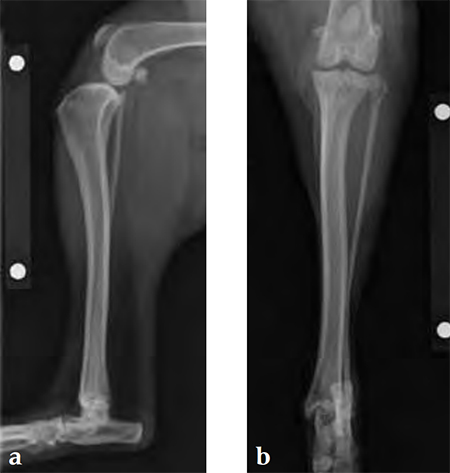

Case 1: English bulldog

(Case provided by Brian Beale, Houston, USA)

A 4-year-old, female, spayed, 33 kg English bulldog had a CrCL tear and a medial patellar luxation. The small stature 3.5 mm TPLO plate was perfect for this dog due to the small profile of the bone and the need to use a heavier plate (3.5 vs a 2.7 mm). In the past, veterinary surgeons have been forced to either squeeze the standard TPLO 3.5 mm plate on the bone or use an undersized TPLO 2.7 mm plate. In this patient, the shorter and smaller profile head of the small stature TPLO 3.5 mm was perfect.